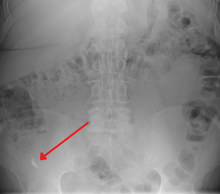

In general, plain abdominal radiography (PAR) is not useful in making the diagnosis of appendicitis and should not be routinely obtained from a person being evaluated for appendicitis.[54][55] Plain abdominal films may be useful for the detection of ureteral calculi, small bowel obstruction, or perforated ulcer, but these conditions are rarely confused with appendicitis.[56] An opaque fecalith can be identified in the right lower quadrant in fewer than 5% of people being evaluated for appendicitis.[39] A barium enema has proven to be a poor diagnostic tool for appendicitis. While failure of the appendix to fill during a barium enema has been associated with appendicitis, up to 20% of normal appendices do not fill.[56]